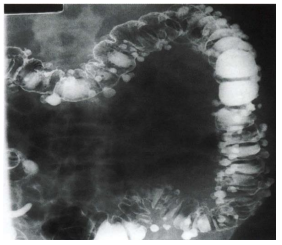

O enema opaco com duplo

contraste ilustrado a seguir evidencia

uma doença bastante prevalente. A

respeito desta doença, assinale a

alternativa CORRETA: